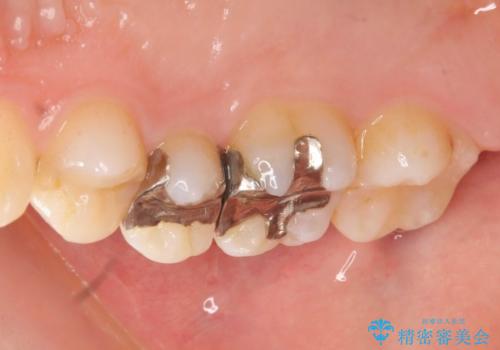

以前治療した歯が痛む 銀歯をセラミックに

- 歯が痛み、改善を求めて来院されました。

歯の神経の治療(根管治療)が必要であることをご説明し、同時に隣在する銀歯の除去も希望されたので同時に治療を行っていきます.

- 27万円(セラミックインレー×2 仮歯・ファイバーコア・ジルコニアクラウン)費用は治療当時の料金となります